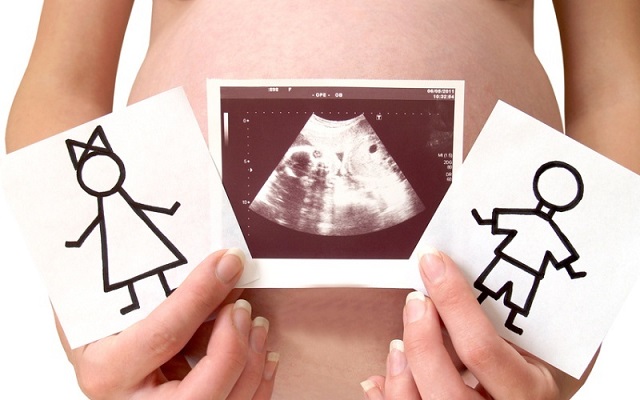

Какая вероятность правильного определения пола на узи

Еще два десятка лет тому назад, врачи с неохотой сообщали пол ребенка. Это считалось блажью и делалось только по большему блату. Сейчас доктора обязательно проинформируют родителей, кого же им ждать.

Самую точную информацию получают, рассмотрев некую анатомическую подробность у малыша. Если она есть – перед вами мальчик, нет – девочка. Правда, кроха может повернуться к монитору попой, закрыться ножками и тогда увидеть ничего не удастся.

Для опытного узиста это не препятствие. Им обычно достаточно увидеть позу ребенка, его расположение в матке и они с точностью до 60% укажут на пол будущего ребенка. Сделать это можно уже на первом узи в 12 недель. Второе исследование даст более точную информацию.

Ошибки возможны. Для некоторых родителей пол малыша при рождении оказывается полным сюрпризом. Но это — большая редкость.